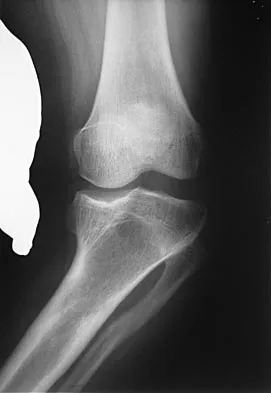

Question 19

Figure 1 shows the radiograph of an 18-year-old patient who has severe knee pain. Treatment consisting of osteotomy should be perfomed